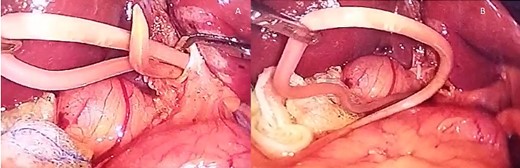

(A) The Ascaris is seen inside the bile duct; (B) the Ascaris is completely removed from the bile duct, choledochotomy is seen as well.

Purulent bile was drained, and a 12 × 1.5 cm A. lumbricoides was found in the bile duct, causing complete obstruction. The roundworm was removed, and a cholangiogram was done afterward, ensuring that the bile duct was clear (Fig. 2a and b).